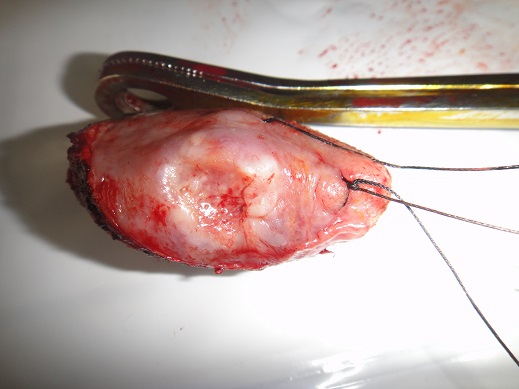

36 years old female suffering from pain in abdomen.on exploration it shows Right Fallopian tube mass.